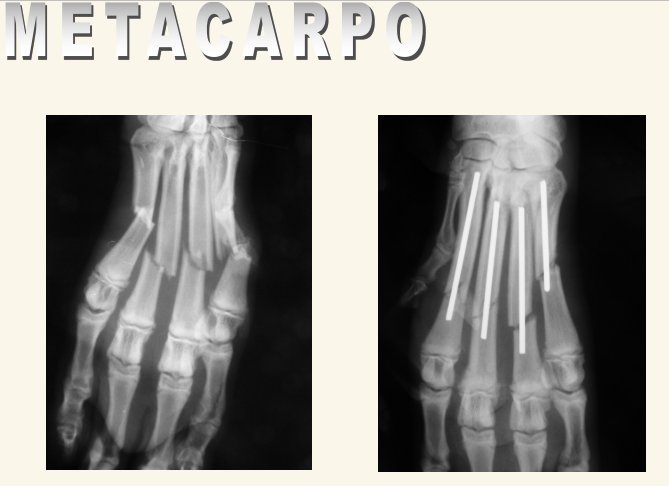

Metacarpo

Si la fractura es solo de uno o dos huesos,se puede sellar solo Sindactilia si faltan huesos

Problemas mas comunes:

- Proyecciones: ML, CdCr

- Fracturas

- Luxación o subluxación

- Sesamoideos múltiples o fragmentados

- Neoplasias: carcinoma de células escamosas, melanoma maligno